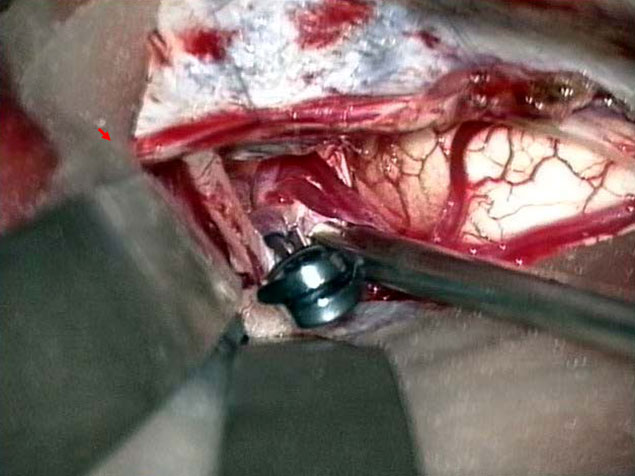

脳動静脈奇形

脳動静脈奇形は先天性の血管奇形のひとつで脳出血や痙攣発作の原因となります。最も基本的な治療法は手術による全摘出ですが、大きさ、発生場所等によっては放射線治療が選択される場合もあります。

当科では放射線治療班と症例検討を行い、個々の患者さんに最も適切は治療を提供しています。 脳動静脈奇形の手術では、術中脳血管撮影を常に行い、全摘出を確認しています。また場合によっては脳動脈瘤手術同様に電気生理学的モニタリングも併用し、確実、安全な手術を行っています(図7、8)。